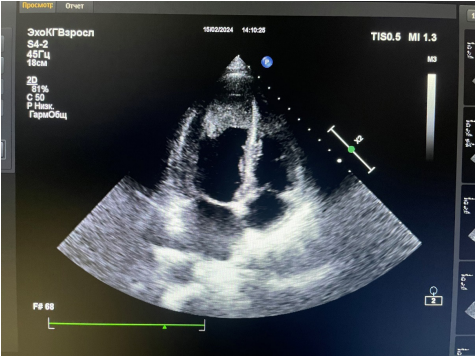

Краткое описание. Молекулярно-генетическое обследование подтвердило мутацию (p.Tyr43Ser) в этом гене, которая также обнаружена у родной сестры и матери ребенка. В процессе наблюдения, во время проведения наркоза у мальчика произошла остановка сердца, обусловленная резкой брадикардией и асистолией, в связи с чем пациенту имплантирован кардиовертер-дефибриллятор.

Краткое описание. Нами представлен случай этаноловой септальной аблации (ЭСА) у пациента женского пола с генетически подтвержденной БФ и симптоматической многоуровневой внутриполостной обструкцией. Ей проведена транскатетерная ЭСА с последующим устранением средне-желудочковой обструкции и обструкции выносящего тракта левого желудочка. Гемодинамический эффект сохранялся в течение последующих 3 мес. наблюдения.